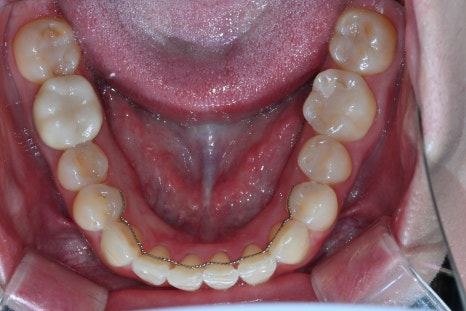

치료 전, 후 비교

<BEFORE>

이 케이스에서는 총 6개 영역을 디자인했습니다.

1.기존 크라운 제거 후 치아 상태 재확인

변색과 경계 문제를 해소하기 위해 기존 보철물 제거 후 잇몸 라인과 치아 모양을 새롭게 설계했습니다.

2.오브제로 퓨어 라미네이트 4개 지대치 형성 및 스캔

가능한 범위 내에서 삭제량을 줄였고, 구강스캐너로 정확한 형태를 채득했습니다.

3.전치부 크라운 2개 디자인 및 인상 채득

앞니 중심축과 교합 높이를 정확하게 형성했습니다.